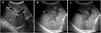

Se realizó ecografía abdominal donde se objetivó hepatomegalia con hipoecogenicidad periportal en porta principal y sus ramas (figs. 1 y 2), y discreta esplenomegalia con múltiples bazos accesorios subcentimétricos en hilio (fig. 3). Se remitió al centro hospitalario de referencia con la sospecha de síndrome mieloproliferativo, donde fue diagnosticado de leucemia mieloide aguda.

Corte transversal-oblicuo del hipocondrio derecho, obtenido mediante sonda convex a nivel de epigastrio, donde se ponen de manifiesto: a) Parénquima hepático de ecogenicidad homogénea (H), venas porta derecha (PD) e izquierda (PI) y vesícula biliar (VB) normales de un paciente sano; b) Parénquima hepático de ecogenicidad heterogénea (H1), venas porta derecha (PD1) e izquierda (PI1) con manguito hipoecogénico (M) en paciente afecto de LMA; c) Imagen similar a la anterior del mismo paciente sin referencias para visualizar mejor las estructuras referidas.